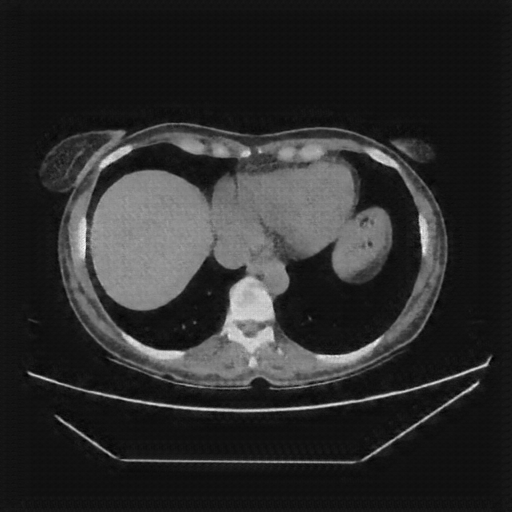

Reconstructed NATIVE CT scan (cycle consistency)

No window - Raw intensity values

Mediastinum window (WL 40, WW 400 β†’ Low βˆ’160, High +240)